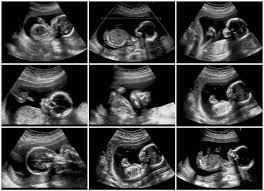

FI dalam USG: 5 Arti Angka Penting yang Ibu Hamil Wajib Tahu!

Saat menjalani pemeriksaan USG kehamilan, Anda mungkin sering mendengar istilah FI dalam USG atau Fluid Index. Angka ini mungkin tampak asing, tetapi sebenarnya memiliki peran vital dalam memantau kesehatan janin. Singkatnya, FI dalam USG adalah ukuran volume cairan ketuban yang mengelilingi bayi Anda di dalam rahim. Cairan ini sangat penting karena berfungsi sebagai pelindung, membantu perkembangan paru-paru dan sistem pencernaan, serta memastikan janin bisa bergerak bebas.

Memahami angka FI dalam USG adalah langkah proaktif bagi setiap ibu hamil. Angka yang berada di luar rentang normal bisa menjadi indikasi adanya kondisi tertentu yang memerlukan perhatian medis. Jadi, mari kita pahami lebih dalam 5 arti angka penting yang perlu Anda ketahui.